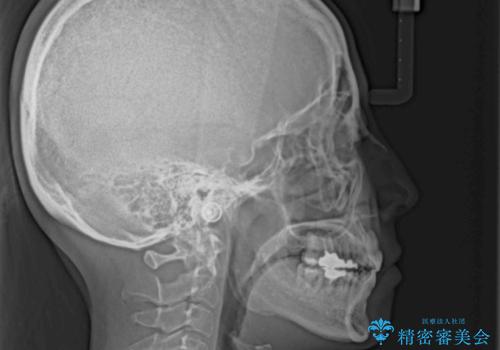

半年もしないうちに八重歯は解消し、治療も当初予定通り2年強で終えることができました。

八重歯・デコボコの解消とともに、前方に張り出した上顎前歯を引っ込めることを目的とし、上下左右の第一小臼歯4歯を抜歯をしてワイヤー矯正により治療することとしました。